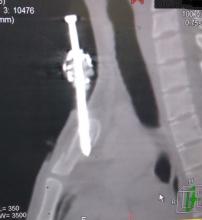

[4]Figure 2. Computed tomography of the chest, sagittal view showing the fired nail traversing the manubrium obliquely with the long axis of the nail parallel to the long axis of the neck. Just the nail tip in the superior mediastinum.

Computed tomography (CT) of the chest with IV contrast revealed a nail penetrating the manubrium (Figure 2). The penetration was in a vertical orientation with slight oblique direction, with the entry point located at the superior end of the anterior plate (about 0.5 cm right of the sternal notch) and penetrating the mid part of the posterior plate as seen in the sagittal view of the CT scan, with just a few millimeters of the nail penetrating into the superior mediastinum. In the sagittal view of the CT scan, one can see fissure fracture of the posterior and anterior plates of the manubrium sterni at separate levels (Figure 2), so the stability of the sternum was not affected.